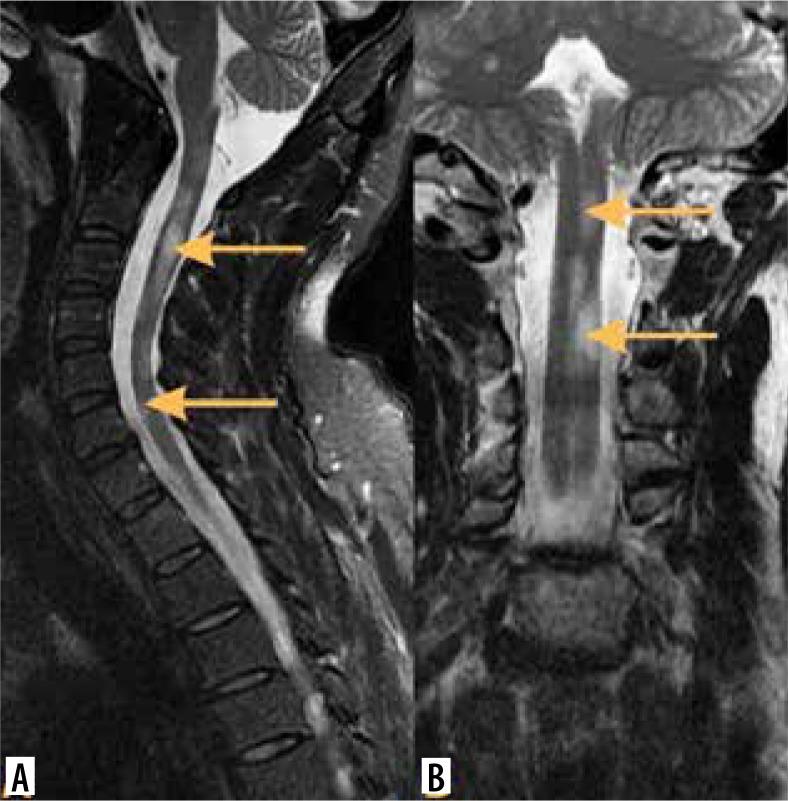

脊髓髓内肿瘤的影像学检查

Imaging of intramedullary tumours of the spinal cord.

Intramedullary tumours (IMTs) are the least common neoplasms of the spinal canal. The majority of them are ependymomas and astrocytomas, the third commonest is haemangioblastoma, while other tumours of the spinal cord are relatively rare. This review presents on update on the imaging of spinal cord tumours. Magnetic resonance imaging (MRI) is the imaging method of choice in diagnosing IMTs, with other modalities playing a supplementary role. The authors discuss the MRI protocol in IMTs including advanced techniques and present the imaging features of particular tumours. The differentiation of IMTs from other spinal cord diseases is also presented.

摘要

髓内肿瘤(IMTs)是椎管内最不常见的肿瘤。其中大多数是室管膜瘤和星形细胞瘤,第三常见的是血管母细胞瘤,而脊髓的其他肿瘤相对少见。本综述介绍了脊髓肿瘤成像的最新情况。磁共振成像(MRI)是诊断IMTs的首选成像方法,其他方式起辅助作用。作者讨论了IMTs的MRI检查方案,包括先进技术,并介绍了特定肿瘤的成像特征。还介绍了IMTs与其他脊髓疾病的鉴别诊断。